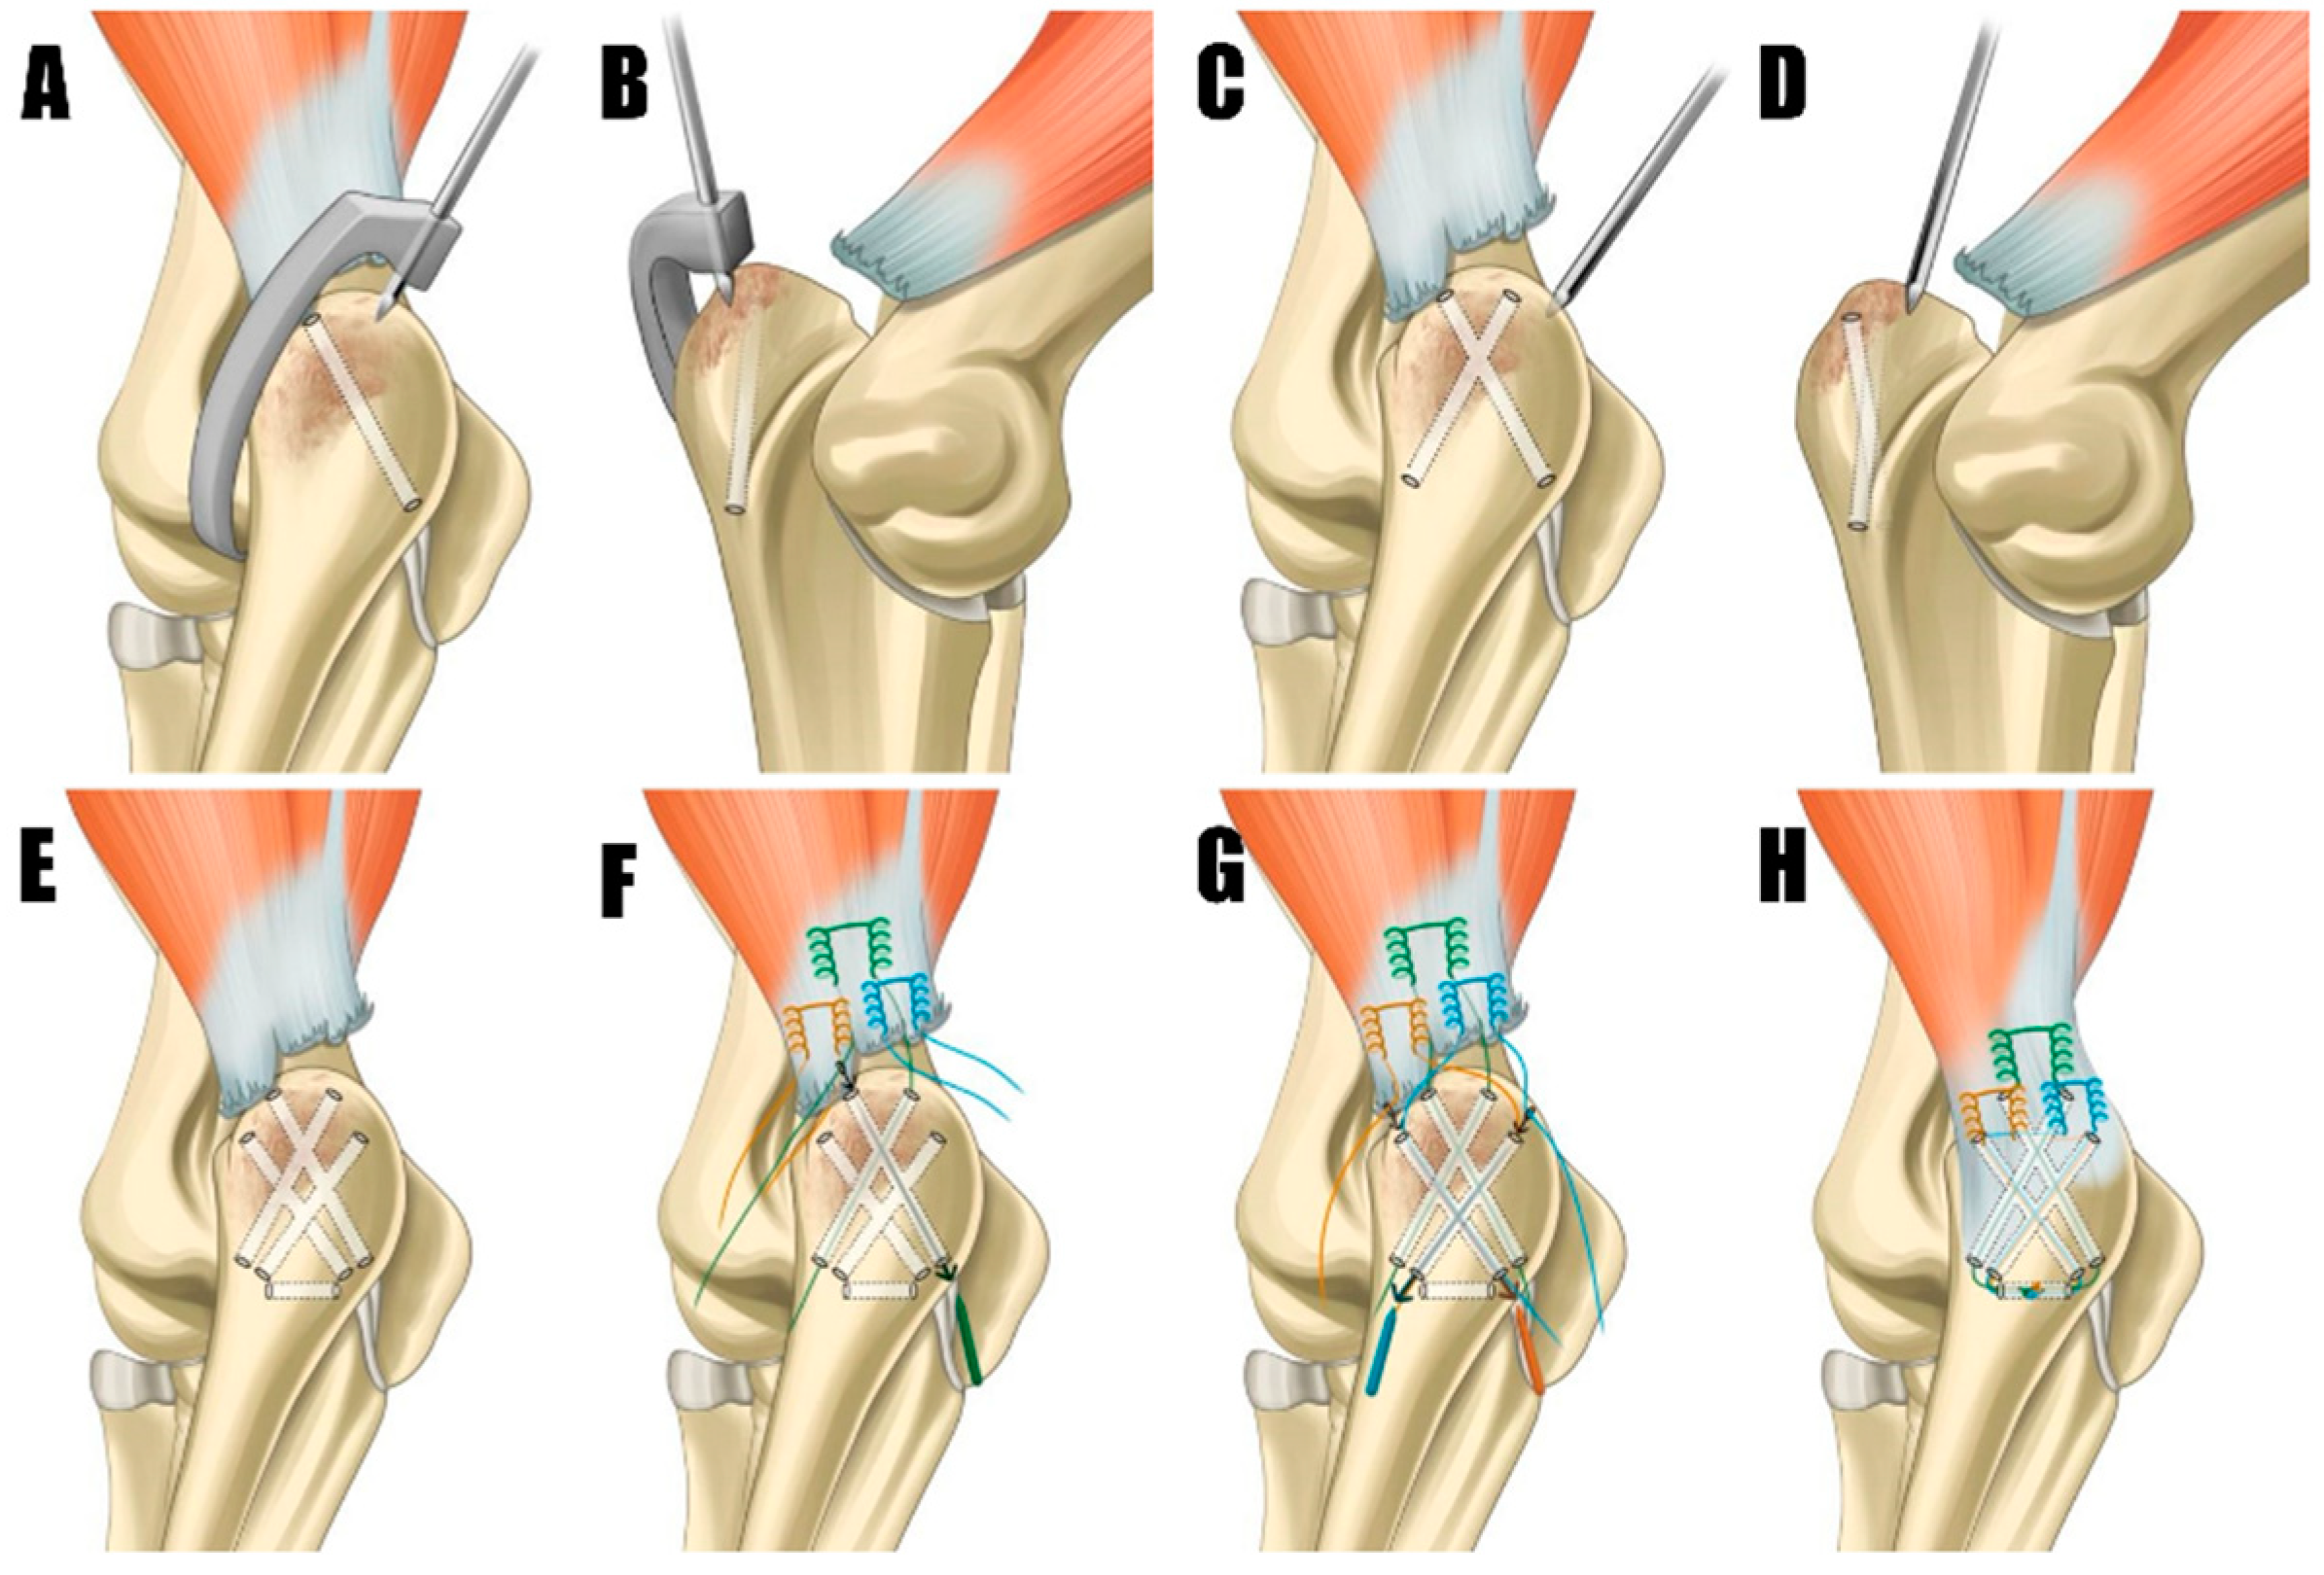

The dog was placed in dorsal recumbency with bilateral elbow joints placed uppermost. To approach the humeroulnar part, a caudolateral approach to the olecranon was made [2]. Fascia were incised and retracted, exposing the triceps brachii tendon and olecranon. Granulation tissue was meticulously debrided with a rongeur and scalpel blade, and the triceps brachii footprint (Figure 3A) on the olecranon was decorticated using an electrically powered oval-shaped burr (Core, Stryker, Kalamazoo, MI, USA) to promote tendon-to-bone healing [12]. The bone tunnel preparation and suture repair technique were adopted from previously reported all-suture repair methods in human medicine, with slight modification. Initially, the origins of the anconeus and flexor carpi ulnaris were elevated from the olecranon to facilitate proper bone tunneling (Figure 4A). Subsequently, two tunnels were created on the craniomedial and craniolateral aspects of the footprint. These tunnels were drilled at 40˚ relative to the proximal anatomic axis of the olecranon, directed caudodistally, using an aiming device and a 1.2 mm Kirschner wire (K-wire) (Figure 4B and Figure 5A,B). The tunnels were drilled to intersect in a “cross” pattern. Similarly, two additional tunnels were created cranially compared to the initial pair, angled approximately 60 degrees to the proximal anatomical axis of the olecranon, to maintain the cross pattern (Figure 4B and Figure 5C,D). The final bone tunnel was drilled transversely across the long axis of the ulna using a 1.6 mm K-wire, serving as an anchorage point for the suture knots (Figure 4C and Figure 5E).

A 2-0 size FiberWire suture (Arthrex, Naples, FL, USA) was employed using a locking Krackow technique (Figure 4D), positioned at the proximal aspect of the tendon. This ensured that enough tendon distal to the suture exits was left to completely cover the triceps brachii footprint. The suture ends were passed through the most craniomedial and craniolateral bone tunnels in a crossing pattern, with the lateral suture end entering the craniolateral hole and exiting caudomedially, and the medial suture ends entering the craniomedial hole and exiting caudolaterally (Figure 5E). Second and third locking Krackow sutures were placed parallel on each medial and lateral side of the triceps brachii tendon’s distal end (Figure 5F). The medial ends of each suture were passed through the caudally positioned craniomedial hole, and the lateral ends through the caudally positioned craniolateral hole, using a suture passer. Three limbs of the suture were threaded through the transverse tunnel (Figure 5H). The suture exiting the proximal aspect of the tendon was tied first, with the elbow in full extension to ensure anatomical reconstruction. After the initial tie, the sutures emerging distally were matched and tied accordingly.

Figure 5. (A,B) These tunnels were originated cranially, employing a C-guide to maintain the integrity of the cross pattern. (C,D) Kirschner wire was used to meticulously create bone tunnels in a cross pattern within the footprint region, directed in craniomedial and craniolateral orientations for suture placement. (E) The final bone tunnel was created transversely along the ulna’s long axis. (F) The application of three Krakow sutures to the tendon, with the most proximal suture (green) passed through the cranial bone tunnel using a suture passer, exiting laterally and medially to enable crossing. (G) Two distal sutures (brown and blue) were passed through the caudal bone tunnels. Each suture’s inner strand was threaded through the bone tunnel on the opposite side to create a crossing configuration. (H) All sutures were passed and crossed through the transverse bone tunnel, forming a knot.